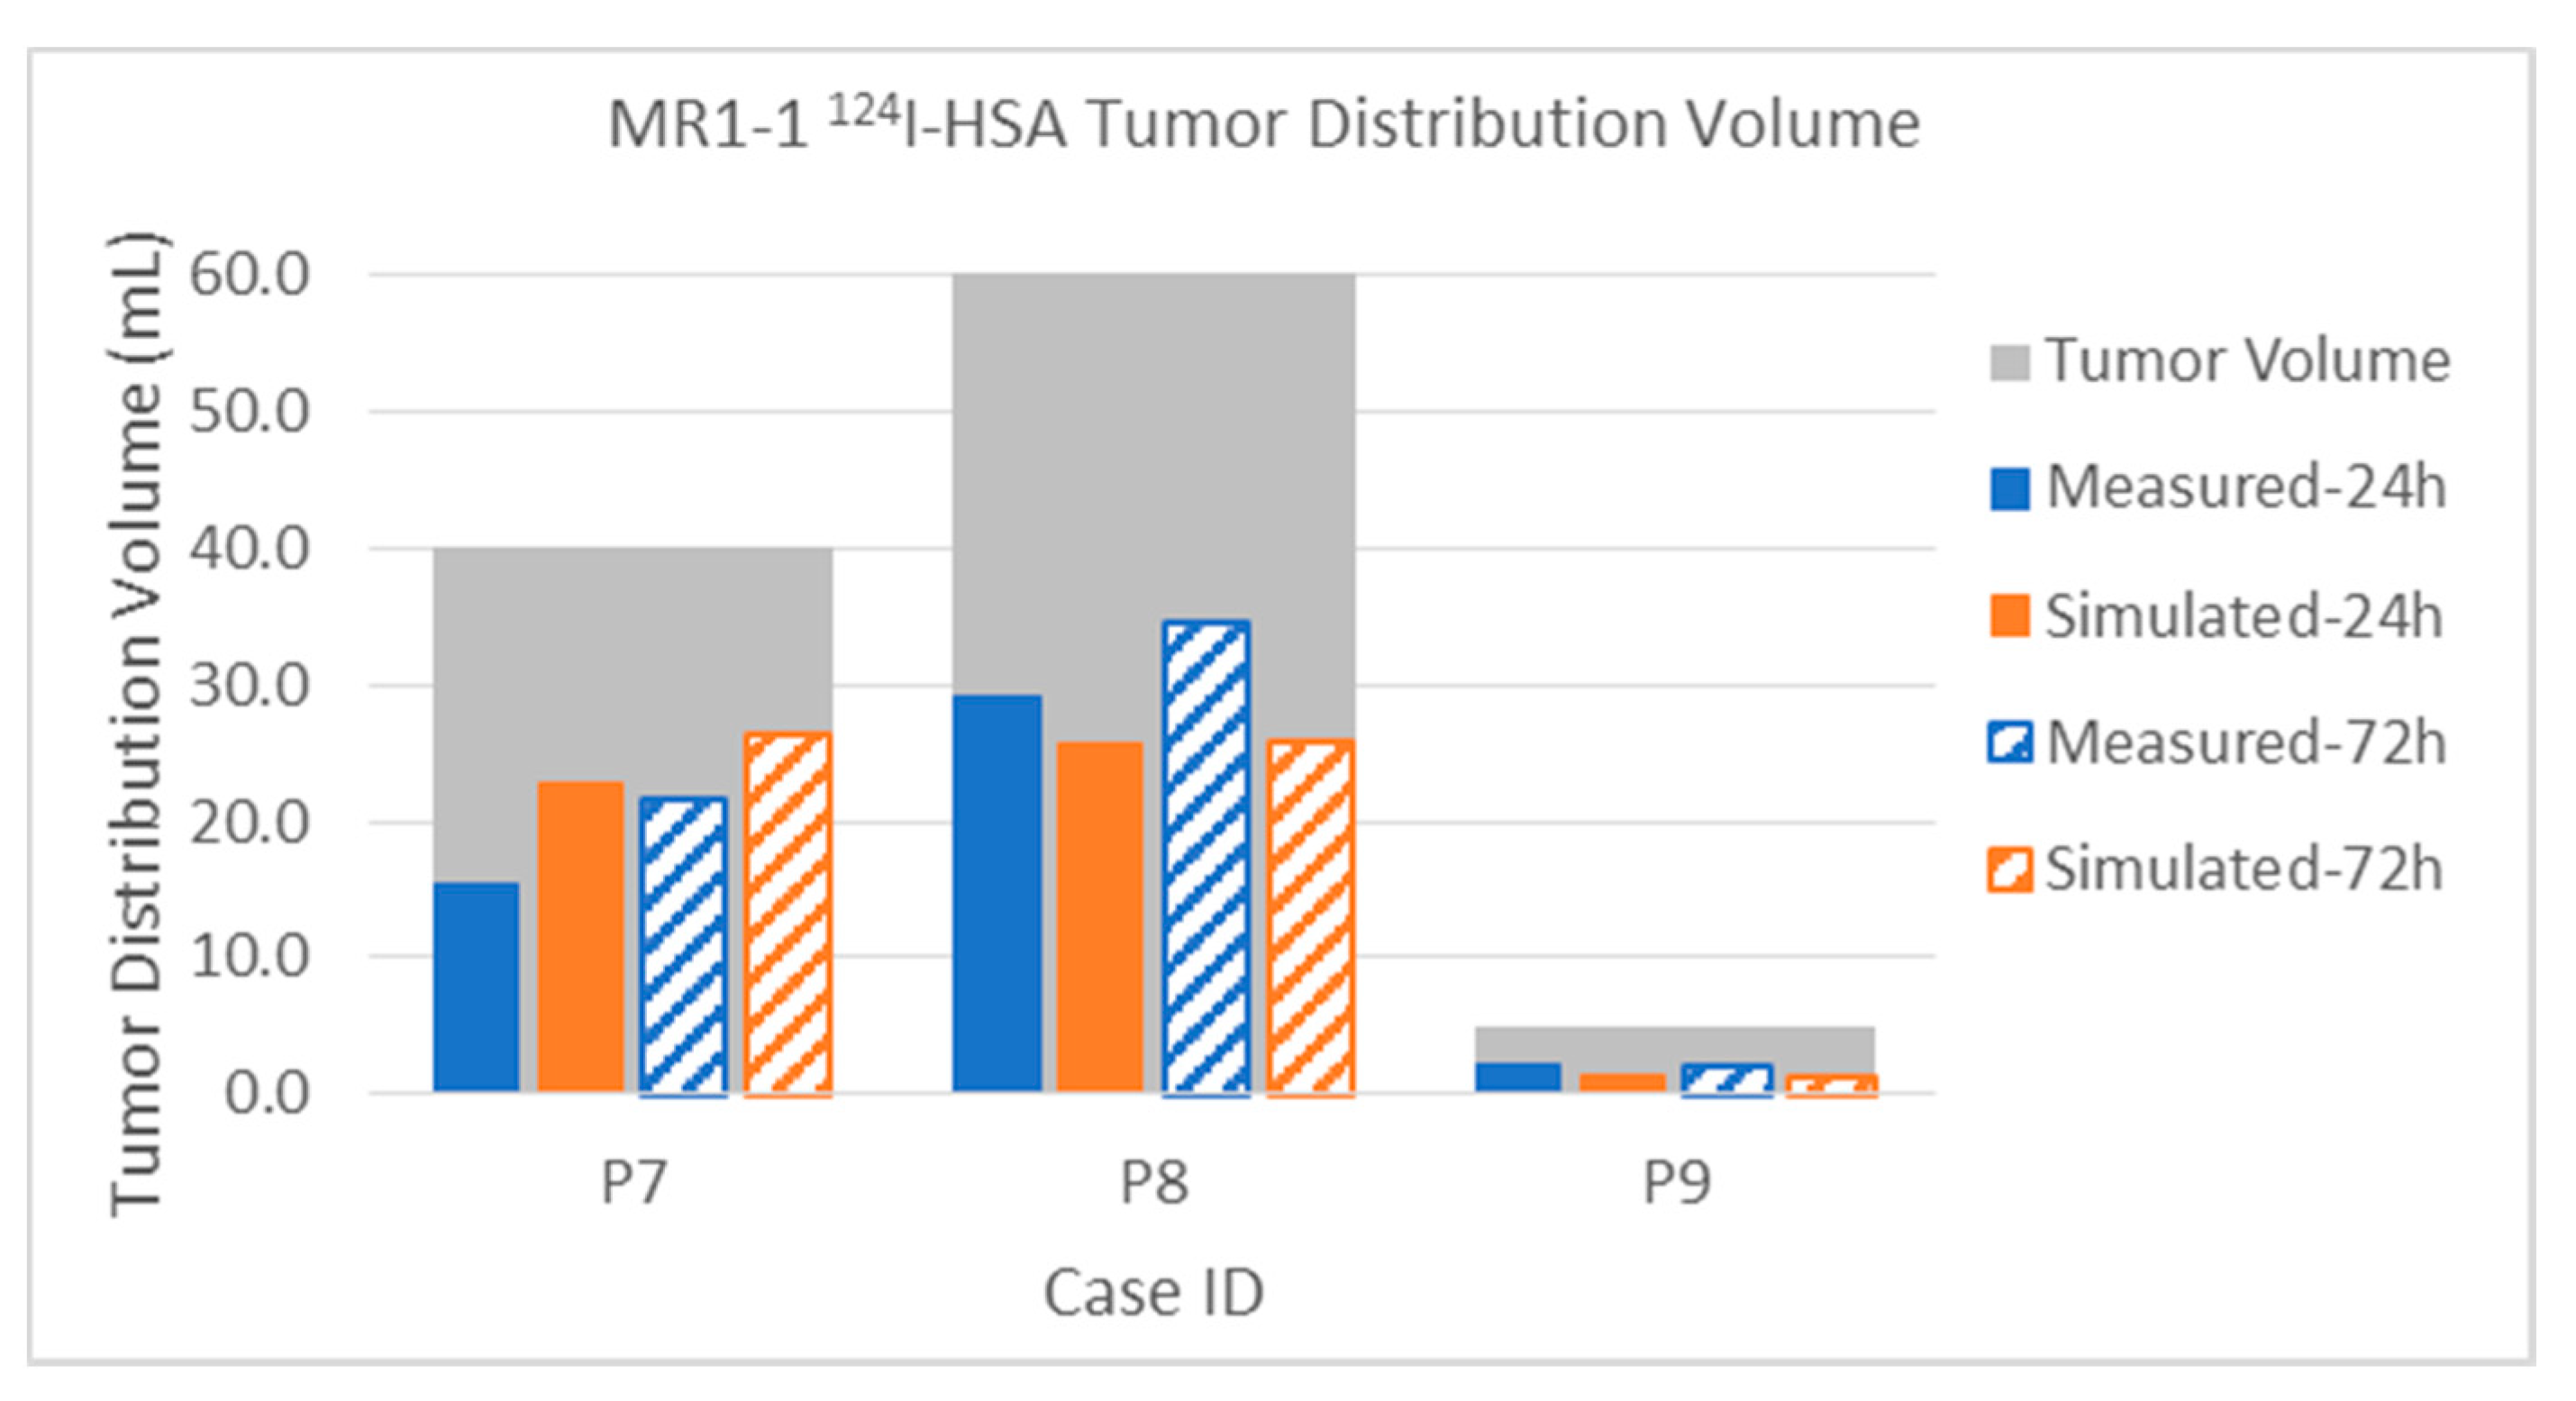

3.2.2. Tumor Distribution Volume

3.2.3. Error Measure

| MR1-1 P07 | Gad | Measured | 5.6 | 6.4 | 38.2 | 45.8 | 48.3 | 70.4 | 14.0% | 16.0% | 22.7% | 27.2% | 40.0 | 168.1 |

| [4] | Simulated | 6.7 | 6.7 | 30.8 | 37.5 | 37.7 | 45.2 | 16.8% | 16.8% | 18.3% | 22.3% | 40.0 | 168.1 | |

| 124I | Measured | 15.3 | 21.7 | 31.3 | 73.6 | 50.1 | 128.6 | 38.3% | 54.3% | 18.6% | 43.8% | 40.0 | 168.1 | |

| Simulated | 22.9 | 26.4 | 45.4 | 70.9 | 69.5 | 104.4 | 57.3% | 66.0% | 27.0% | 42.2% | 40.0 | 168.1 | ||

| 24 h | 54 hr | 24 h | 54 hr | 24 h | 54 hr | 24 h | 54 hr | 24 h | 54 hr | |||||

| MR1-1 P08 | Gad | Measured | 4.3 | 7.0 | 9.8 | 16.7 | 15.4 | 28.2 | 7.2% | 11.7% | 5.3% | 9.0% | 60.0 | 186.2 |

| [4] | Simulated | 4.6 | 4.6 | 11.0 | 12.0 | 15.8 | 17.0 | 7.7% | 7.7% | 5.9% | 6.4% | 60.0 | 186.2 | |

| 124I | Measured | 29.0 | 34.5 | 25.9 | 64.8 | 59.5 | 113.9 | 48.3% | 57.5% | 13.9% | 34.8% | 60.0 | 186.2 | |

| Simulated | 25.7 | 25.8 | 26.8 | 40.2 | 53.6 | 69.2 | 42.8% | 43.0% | 14.4% | 21.6% | 60.0 | 186.2 | ||

| 24 h | 72 h | 24 h | 72 h | 24 h | 72 h | 24 h | 72 h | 24 h | 72 h | |||||

| MR1-1 P09 | Gad | Measured | 0.1 | 0.0 | 24.2 | 0.0 | 29.4 | 0.0 | 2.0% | 0.0% | 45.1% | 0.0% | 5.0 | 53.6 |

| [4] | Simulated | 0.3 | 0.3 | 24.5 | 25.6 | 31.8 | 34.7 | 6.0% | 6.0% | 45.7% | 47.8% | 5.0 | 53.6 | |

| 124I | Measured | 2.1 | 2.2 | 35.2 | 32.5 | 47.3 | 39.4 | 42.0% | 44.0% | 65.7% | 60.6% | 5.0 | 53.6 | |

| Simulated | 1.4 | 1.4 | 28.3 | 30.3 | 37.8 | 42.9 | 28.0% | 28.0% | 52.8% | 56.5% | 5.0 | 53.6 | ||